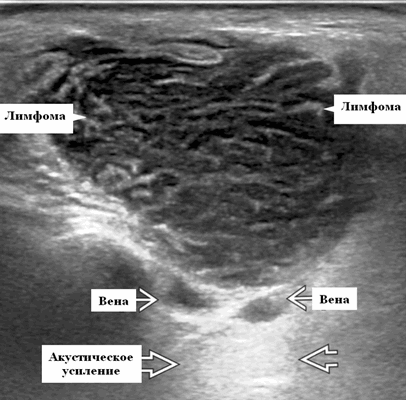

- Узловая неходжкинская лимфома (НХЛ): одиночные или множественные увеличенные яйцевидные внутрипаротидные лимфатические узлы, которые на УЗИ гомогенно гипоэхогенны по отношению к паренхиме околоушной железы, эхо-картина сетчатая. Заднее акустическое усиление. Выраженная внутриузловая гиперваскуляризация

Лучший диагностический признак на УЗИ при узловой НХЛ: множественные однородные, четко выраженные образования околоушных желез и лимфаденопатия верхних отделов шеи. Паренхиматозная НХЛ: инфильтративная околоушная опухоль, фон СШ, BLEL

Серошкальное УЗИ. Узловая НХЛ. Одиночные или множественные увеличенные яйцевидные внутрипаротидные лимфатические узлы. Гомогенно гипоэхогенный по отношению к паренхиме околоушной железы. Сетчатый эхосигнал. Заднее акустическое усиление. Первичная паренхиматозная НХЛ. Рассеянный, неоднородный эхосигнал; нечеткие, гипоэхогенные, похожие на опухоль участки. В пунктате внутрикистозная или паренхиматозная кальцификация из-за конечной стадии воспалительного изменения. Небольшие кистозные области образуются из-за сдавления терминальных протоков лимфоидной гипертрофией. Множественные небольшие гипоэхогенные участки (представляют собой лимфоидные агрегаты), разбросанные на фоне ткани слюнной железы. Изменения могут имитировать хронический сиалоаденит и диагноз часто ставится при биопсии. На УЗИ необходимо искать аналогичное поражение других слюнных и слезных желез, фон синдром Шегрена, BLEL. Может иметь или не иметь перипаротидную и шейную лимфаденопатию